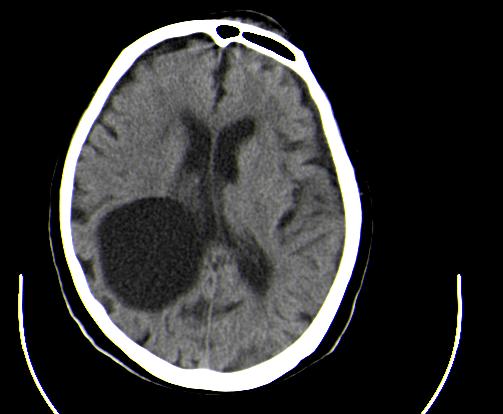

患者男性,67岁,头晕摔倒后来医院就诊,患者诉平时体健,否认有颅内病变史

定位:右侧脑室三角区扩大,呈球形,侧脑室颞角扩大,右侧脑室内占位:

定性:蛛网膜囊肿可能性大;

定位:右侧脑室三角区扩大,呈球形,侧脑室颞角扩大。

考虑:1、右侧侧脑室三角区室管膜囊肿?皮样囊肿?

2、脑萎缩。

神经上皮囊肿为先天性疾病,可发生在脉络丛、脑室内、脉络膜裂,少数位于脑质内,侧脑室三角区最为常见。按发生部位和囊壁的细胞学类型可有不同的命名。位于脉络丛者为脉络丛囊肿,常两侧同时发生。脑室内者为室管膜囊肿,多位于侧脑室三角区。脉络膜裂囊肿可以是神经上皮囊肿,也可以是蛛网膜囊肿。 囊肿呈脑脊液样低密度,边界清楚整齐。患者多无症状,有症状者多为头痛、癫痫发作。囊壁很薄,ct一般不能显示,囊壁无钙化。囊肿可有占位效应,表现为相应部位的脑室或脉络膜裂较对侧扩大,脑实质受压,一般不引起脑水肿。增强:囊肿及囊壁均无强化。

与蛛网膜囊肿的鉴别:蛛网膜囊肿好发于中颅窝、鞍上、半球、后颅窝、侧裂,脑室内少见,临床表现和影像学与神经上皮囊肿无明显差别。主要靠发病部位鉴别。